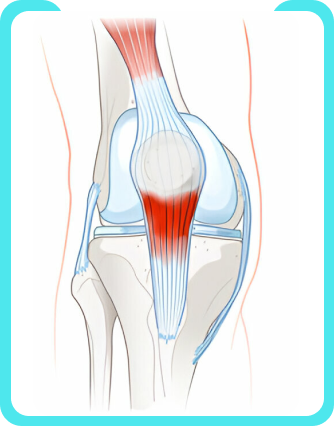

Patellar tendonitis is a common injury or inflammation of the tendon that connects your kneecap (patella) to your shinbone (tibia). Your pain may be mild or severe.

Patellar tendonitis comes from repetitive stress on the knee, most often from overuse in sports or exercise. The repetitive stress on the knee creates tiny tears in the tendon that, over time, inflame and weaken the tendon.

Pain and tenderness at the base of your kneecap are usually the first symptoms of patellar tendonitis. You may also have some swelling and a burning feeling in the kneecap. Kneeling down or getting up from a squat can be especially painful.